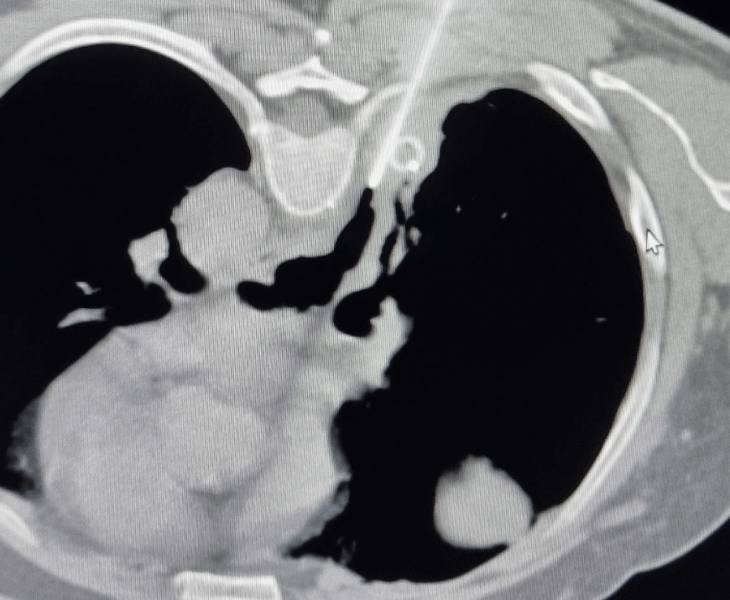

Chest & Mediastinal Drainage

Drainage procedures to relieve collections in the chest/mediastinum under CT guidance.